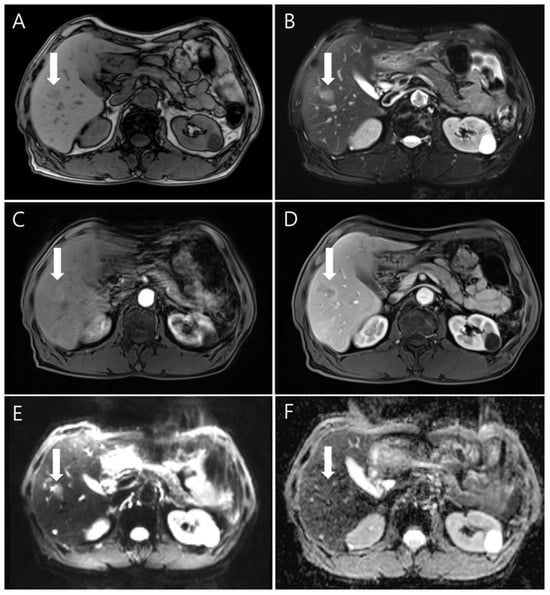

Liver magnetic resonance imaging (MRI) was performed to differentiate the pulmonary and hepatic lesions from another possible diagnosis. It revealed a 1.5 cm ill-defined nodular lesion contiguously extending into the liver capsule (Figure 4). These findings mostly likely represented liver fluke disease. The diagnosis of toxocariasis was confirmed through the presence of antibodies to Toxocara canis by enzyme-linked immunoassay (ELISA). Other parasite antibody tests, including Clonorchiasis sinesis, Paragonimus westermani, Taenia solium, Spirometra mansoni, Fasciola hepatica, Amoeba, Trichinella spiralis, and Schistosoma, all yielded negative results. Eventually, his colon cancer was treated with laparoscopic low anterior resection. After discharge, the patient took oral albendazole by himself. After 3 months, chest and abdominal CT was performed for the postoperative routine follow-up, and it showed a shrinkage of all pulmonary and hepatic lesions compared to the previous imaging. Finally, after 5 months, the entire multiple cavitary lung and the hepatic nodules disappeared (Figure 2 and Figure 3). In addition, the eosinophil ratio decreased from 6.6% to 0.4%.

Figure 4.

The gadolinium-enhanced dynamic MRI findings showed the nodule (white arrows) with low signal intensity on the unenhanced T1-weighted image (A) and high signal intensity on an unenhanced T2-weighted image (B). In dynamic imaging, the lesion showed slightly high signal intensity in the arterial phase (C) and rim enhancement in the portal venous phase (D). Diffusion-weighted imaging (E) showed indistinct high signal intensity; the apparent diffusion coefficient mapping imaging (F) was isointense.